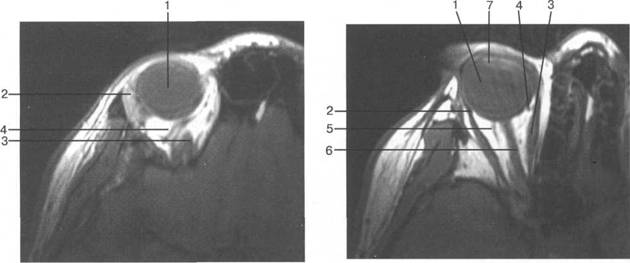

орбитальная клетчатка 4 3

(corpus adiposum orbitale).

HU), каплив 121h711b ают контрастный препарат. Толщина хнюю прямую мышцу видно плохо, обычно ее изображение слив 121h711b ается с изображением мыш­

На КТ-изображениях глазное яблоко имеет шаровидную структуру, четко выраженную обо­лочку, внутри его определяется хрусталик эллиптической формы размером 4x9 мм, плотностью

четлив 121h711b о дифференцировать зрительный нерв и глазодвигательные мышцы (рис. 2.16, 2.17).

V

нижняя косая мышца отчетлив 121h711b о